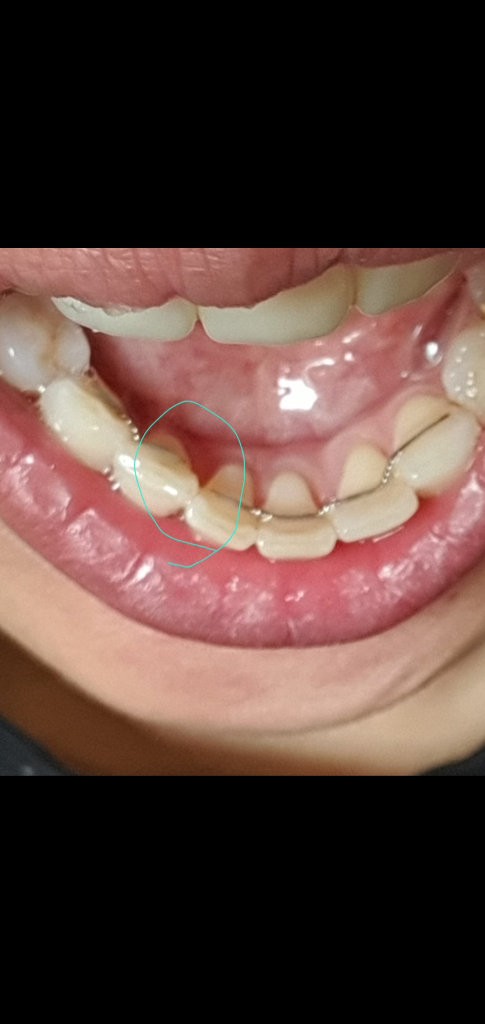

7일 아랫니 고정식유지장치 한곳이 끊어져

치과에서 그부분만 제거하고 11일에 다시 본뜨고 다시 제작하여 새로 부착하기로했습니다.

10년이나 지나서 그런지 이미 치열은 틀어졌습니다.

3. 고정식유지장치를 지금 이상태로 놔두고 가철식 유지장치만 새로 맞춰 끼고 있어도 괜찮을까요?

- 고정식 유지장치를 두고 하셔도 되지만, 그렇게 두개를 동시에 하실필요는 없을꺼 같습니다.